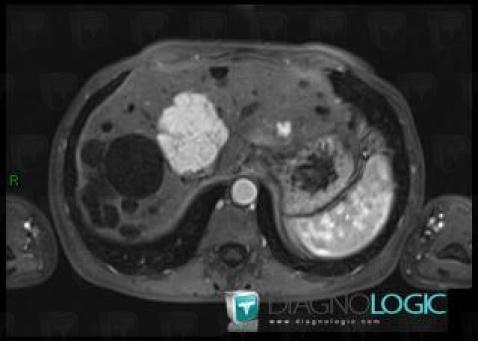

Hyperplasie nodulaire focale, Foie, IRM

Voici les informations spécifiques à l'image clé ci dessus:

- Diagnostic Hyperplasie nodulaire focale, Localisation(s) Foie, comportant les gammes Lésion hépatique en hypersignal T2

Polykystose rénale, Foie, IRM

- Diagnostic Polykystose rénale, Localisation(s) Foie, comportant les gammes Lésion hépatique en hypersignal T2

- Diagnostic Polykystose rénale (lié à Polykystose hépatique), Localisation(s) Foie, comportant les gammes Lésion hépatique kystique